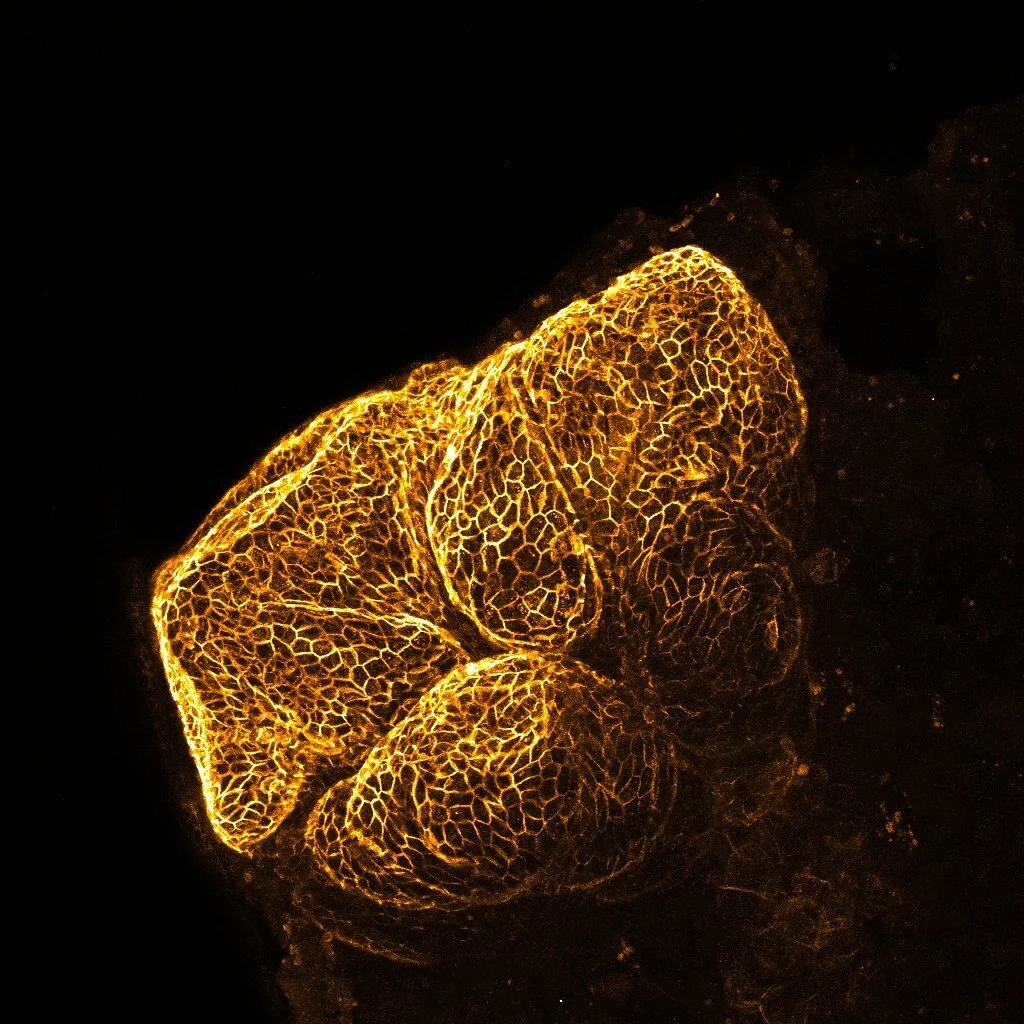

In the liver, bile ducts form from a group of cells known as hepatoblasts. To form a duct, hepatoblasts form a transient structure known as the ductal plate that further develops into the biliary tree. Using a combination of human genetics and transgenic animal models, we know that a small number of signals are necessary for bile duct cells (cholangiocytes) to form. What is not very clear is what happens to these cells once they have been generated and what signals drives them to form ducts.